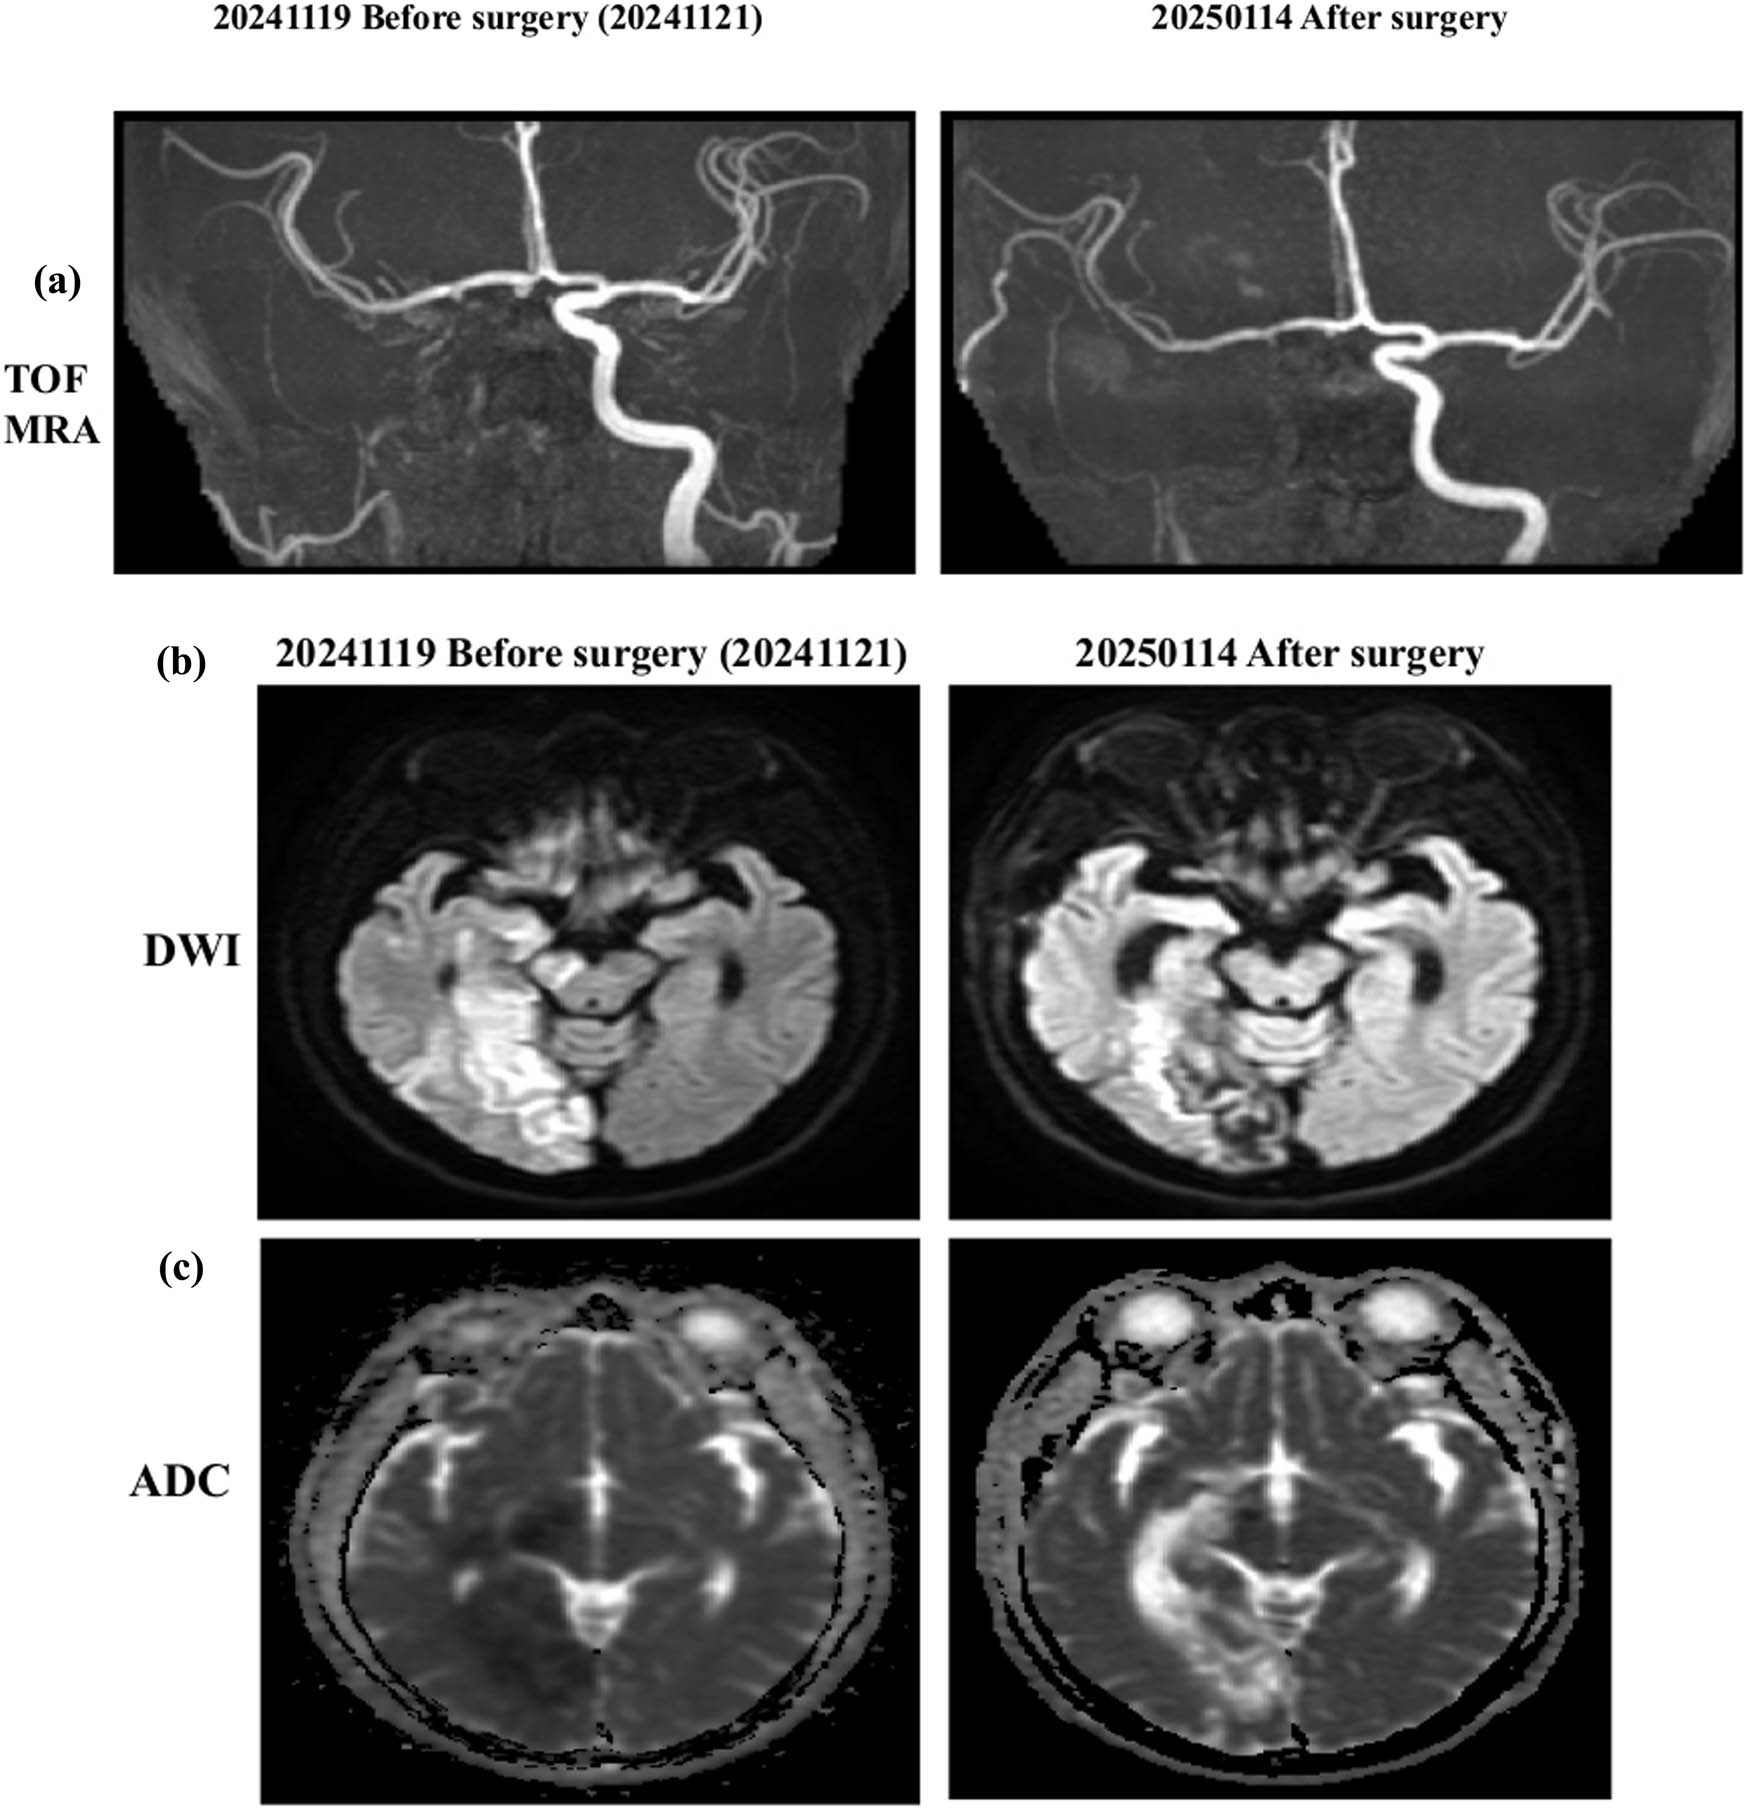

On November 21, 2024, the patient underwent a superficial temporal artery to middle cerebral artery (STA–MCA) bypass procedure (Figures 3 and 4). The initial postoperative course was uneventful; however, substantial neurological deficits persisted despite surgical revascularization. As part of adjunctive therapy, molecular hydrogen supplementation was initiated from November 13, 2024, to January 13, 2025 (2 months). This was followed by 10 days of one hydrogen with rhodiola capsule daily (PURE HYDROGEN, HoHo Biotech Co., Ltd., Taipei, Taiwan), each containing 170 mg of hydrogen-rich coral calcium, corresponding to approximately 1.7 × 1021 molecules of molecular hydrogen), after which a third blood test was conducted. The hydrogen with rhodiola therapy was then extended for an additional 2 months (PURE HYDROGEN), each containing 170 mg of hydrogen-rich coral calcium, corresponding to approximately 1.7 × 1020 molecules of molecular hydrogen, and 100 mg of rhodiola rosea extract.

Serial neuroimaging before and after STA–MCA bypass surgery. (a) TOF MRA performed on November 19, 2024 (preoperative), demonstrates occlusion of the right ICA with reduced distal perfusion. Follow-up MRA on January 14, 2025 (postoperative), shows improved collateral circulation in the MCA territory, consistent with successful revascularization via STA–MCA bypass. (b) Diffusion-weighted imaging (DWI) prior to surgery reveals hyperintense signals in the right hemisphere, indicating acute ischemic changes. Postoperative DWI shows no new hyperintensities, suggesting the absence of additional infarcts. (c) Apparent diffusion coefficient (ADC) maps demonstrate corresponding preoperative hypointensities, confirming restricted diffusion in infarcted regions. Postoperative ADC findings reflect infarct maturation without evidence of extension.

Cerebral vascular imaging before surgery confirmed right ICA occlusion prior to the procedure. On November 13, 2024, postoperative imaging following STA–MCA bypass demonstrated enhanced cerebral perfusion, with no evidence of new ischemic lesions, indicating the absence of perioperative infarction (Figure 4). On January 13, 2025, adjunctive therapy with hydrogen–rhodiola capsules was administered. On March 13, 2025, after two months of adjuvant therapy with hydrogen-rhodiola capsules, postoperative imaging demonstrated improved cerebral perfusion, correlating with the notable neurological recovery of the patient. Specifically, motor function improved from severe left-sided weakness (Medical Research Council grade 1) to near-complete recovery, with MRC grade 5 in the left upper limb and grade 4 in the left lower limb.